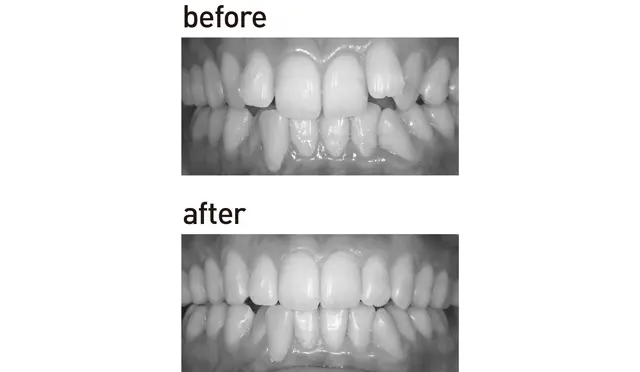

裏側部分ワイヤー矯正

人から気づかれずに部分的な歯並びを治すなら

歯の裏側にブラケット(ワイヤーを通すための装置)とワイヤーを装着。部分的な矯正も可能で、強い力で歯を効率よく動かせるうえ、装置が目立たないことがメリット。ただ表側に比べ期間が長く費用も高め。取りはずし不可なので、歯周病のリスク予防に、矯正中はよりてねいな歯磨きを。目安は部分矯正で¥440,000〜。